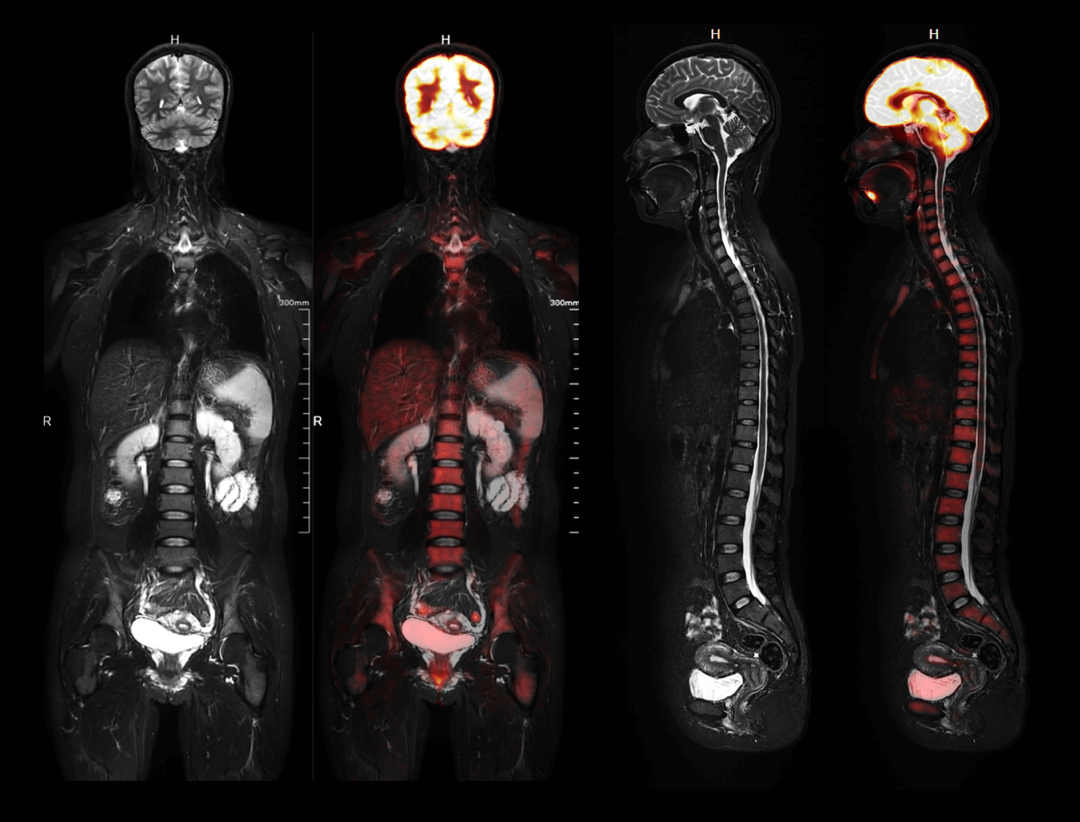

Whole-body Imaging with 4 bodies comparison

Whole-body Imaging